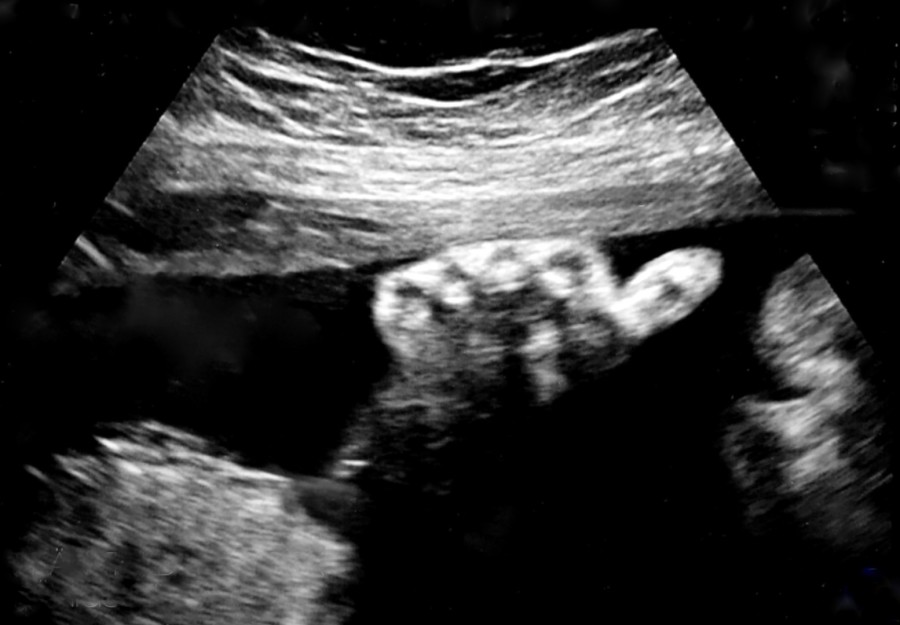

Sog. "Facing" beim Feinschall der Stufe II. Seltene Aufnahme: Die rechte Hand mit allen 5 Fingern ist hier gleichzeitig mit dem Gesicht getroffen.